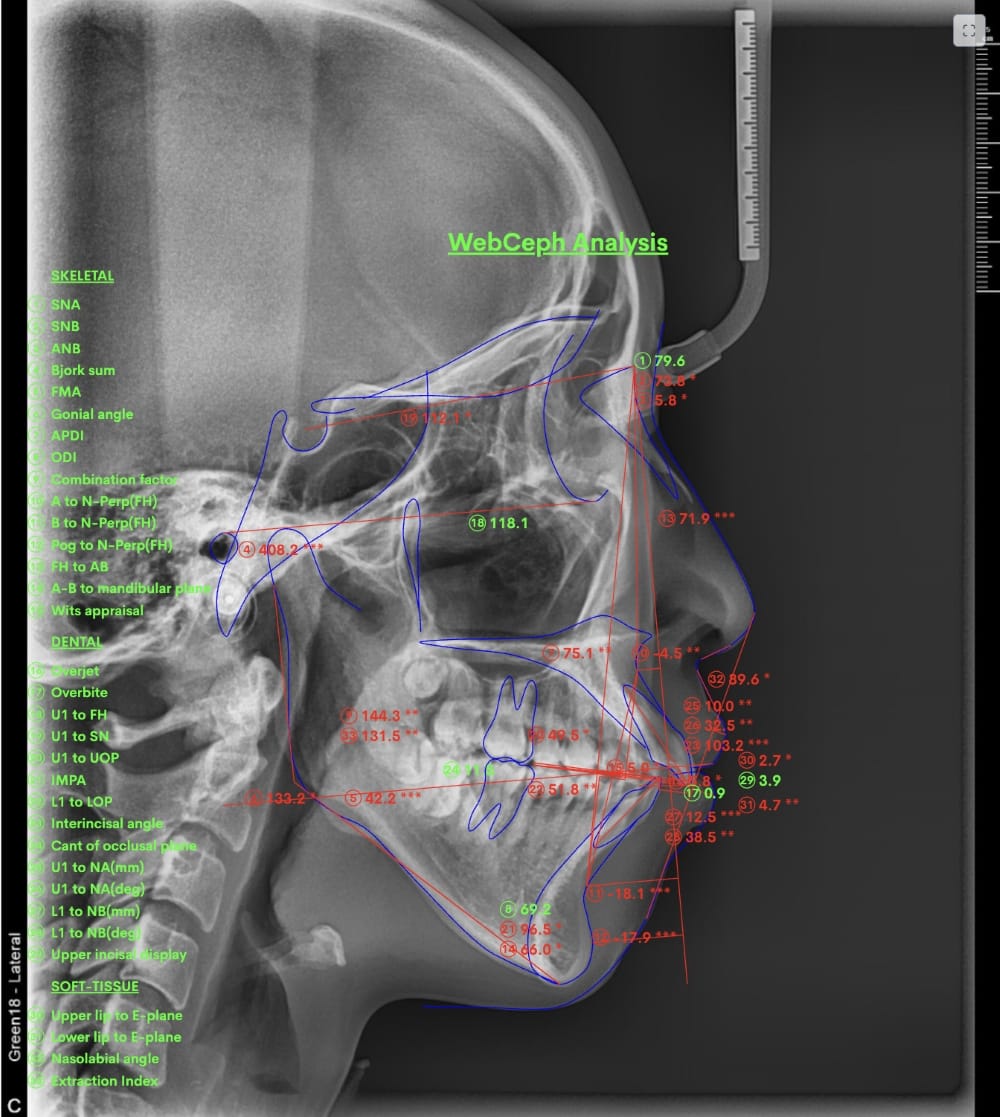

② セファロ(横顔レントゲン)分析

骨格的な問題があるかどうかを数値で評価します。

上顎・下顎の前後関係、前歯の傾斜角度、口元の軟組織のバランスなどを客観的に確認することで、「歯が原因なのか」「骨格が原因なのか」を明確にします。

- セファロによる骨格診断